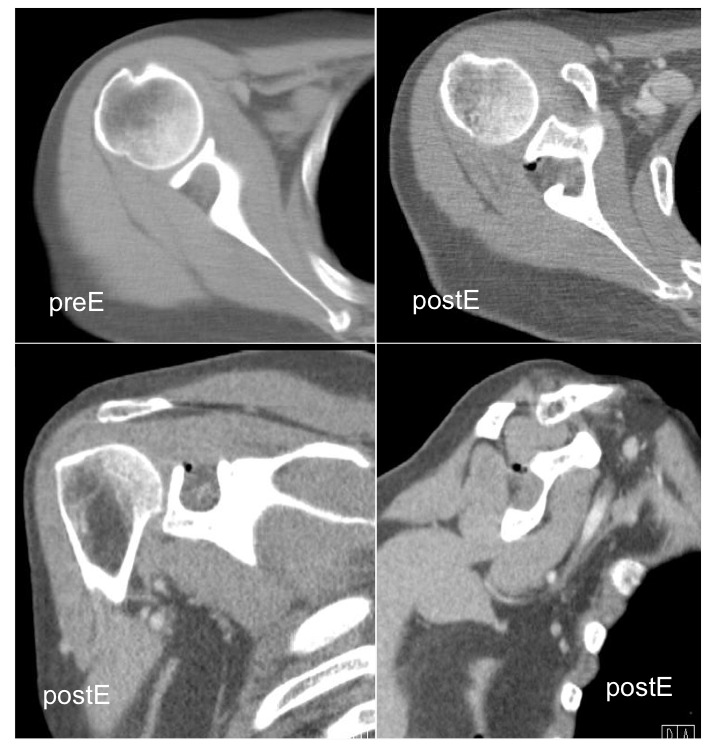

Inflammatory Myofibroblastic Tumor; WHO classify inflammatory myofibroblastic tumor as a distinct borderline lesion with uncertainty as to whether it is reactive or neoplastic; characterized histologically by the presence of acute and chronic inflammatory cells with a variable fibrous response

inflammatory pseudotumor ( RID3860 )